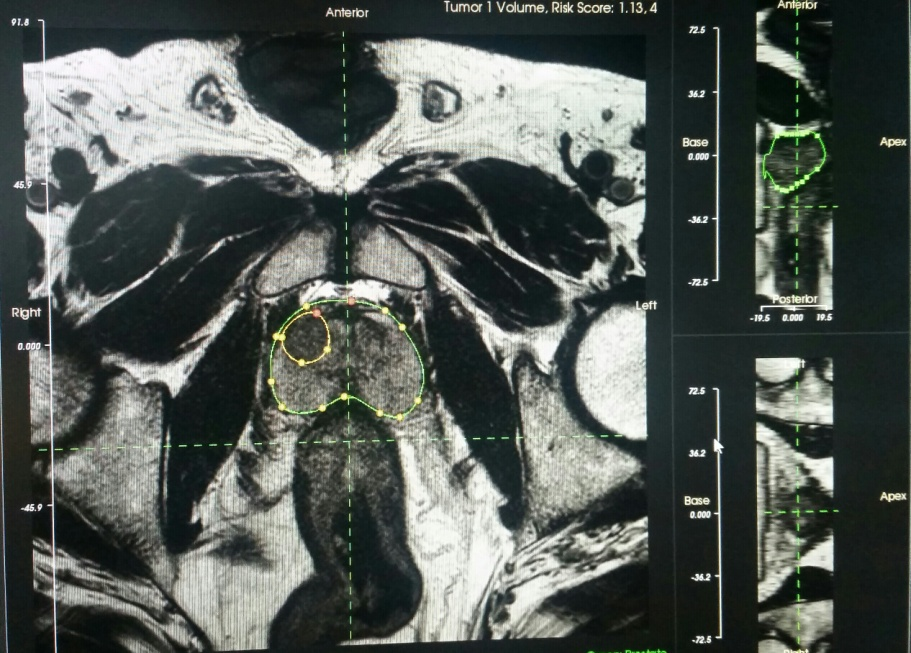

Con tale metodica e in pazienti selezionati (già precedentemente sottoposti a biopsia prostatica risultata negativa), oggi è possibile eseguire delle biopsie mirate superselettive su aree prostatiche sospette. Tutto ciò mediante un software che consente la fusione dell’immagine ecografica e dell’immagine di risonanza magnetica fornita grazie alla collaborazione con i medici del reparto di Radiologia diretto dal dottor Alessandro Leone.